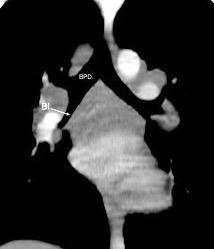

En el normal, el bronquio intermediario (BI) aparece en la proyección lateral, como una línea fina vertical que cruza el bronquio del LSI en su unión con el principal. (BPI) Engrosamiento del bronquio intermediario (BI)

Schnur MJ et al.. Thickening of the Posterior Wall of the Bronchus Intermedius. Radiology. 1981

Fallo cardiaco

MJ et al.. Thickening of the Posterior Wall of the Bronchus Intermedius. Radiology. 1981 Ca. microcítico